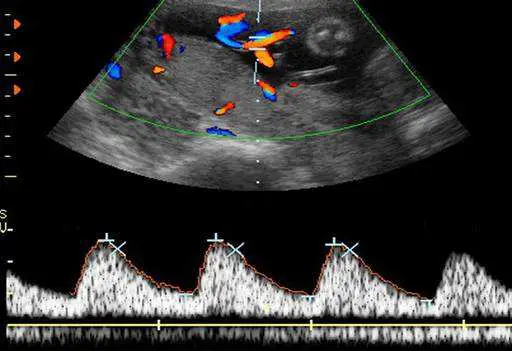

承上題【21 歲孕婦,G1P0 ,妊娠 38 週,接受杜卜勒超音波檢查,結果如圖所示,其檢查名稱為下列何者?】,S/D ratio 為 2.5 ,檢查結果為何?

本題承接前一題(臍動脈杜卜勒超音波檢查),考核考生判讀臍動脈杜卜勒波形(umbilical artery Doppler)的能力。核心概念為:在妊娠 38 週時,S/D ratio = 2.5 代表什麼臨床意義?需區分正常(normal)、舒張末期血流消失(absent end-diastolic velocity, AEDV)與舒張末期血流逆流(reversed end-diastolic velocity, REDV)三種狀態。

影像分析:

圖片為彩色血流杜卜勒超音波影像,分為上下兩個部分:

上半部(彩色血流影像):顯示胎兒腹部橫切面,可見臍帶血管以橘紅色(代表朝向探頭的血流)及藍色(代表遠離探頭的血流)呈現,血管走向正常,與圓形胎兒腹部截面相鄰,符合臍動脈彩色血流掃描的標準擺位。

下半部(頻譜杜卜勒波形):顯示典型的臍動脈脈衝波杜卜勒(pulsed-wave Doppler)波形。波形特徵如下:

- 收縮峰(systolic peak, S):明顯高聳的週期性波峰,代表心臟收縮期血流速度

- 舒張末期血流(end-diastolic velocity, EDV):波形基線之上仍有持續正向血流,清晰可見舒張期波谷高於零基線,表示胎盤血管阻力正常

- 波形規律:三個週期的波形形態一致,S/D 比值經